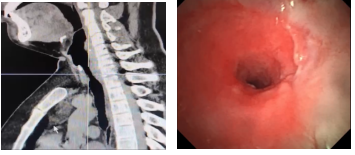

入院后,患者完善胸CT和气管镜检查显示,在声门下约2 cm处存在气管狭窄,长度约3.5 cm,最窄处仅4 mm,并且有逐渐回缩趋势。

难点5:气管狭窄位置高,位于声门下2cm;长度长,狭窄长度约3.5cm;狭窄重,最小直径约4mm。之前反复治疗导致狭窄近端瘢痕组织厚,质地韧,扩张过程中气管撕裂、纵隔气肿风险高,远端气管软骨断裂,软化塌陷,硬镜难以推送至理想位置。